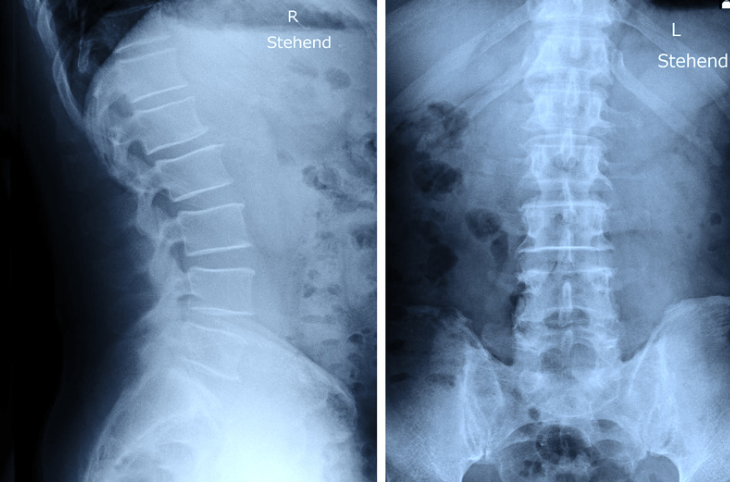

高齢の方の慢性的な腰痛の場合、変形性腰椎症の場合が多いです。基本的にレントゲンを撮って、腰骨の正面と側面、また前かがみや後ろに反らした状態で腰の並びやずれがないかをチェックします。

腰部脊柱管狭窄症の診断

足のしびれ痛みの範囲、は行(歩いてどんどん痛くなること)の有無、足に力が入るかをチェックします。足の血管が詰まっても同じような症状となるので、足の甲の動脈が触れるかを確認することもあります。レントゲンで腰骨の並びもチェックしますが、神経の通り道が本当に細くなっているかはMRIを撮像しないとわからないため、症状が酷い方にはMRIを撮ることを推奨してます。

腰椎圧迫骨折の診断

診断はレントゲンで行います。正面と側面を確認し、つぶれている腰骨がないかチェックします。腰骨がつぶれてなくても安心はできず、不顕性骨折と言ってレントゲンでわからない骨折もあるので、痛みが強い場合はMRIで診断することもあります。

変形性足関節症の診断

足首の痛みの場所や可動域の確認します。次にレントゲン、特に体重をかけた時のレントゲン画像で足首の関節の隙間があるかどうかを確認します。